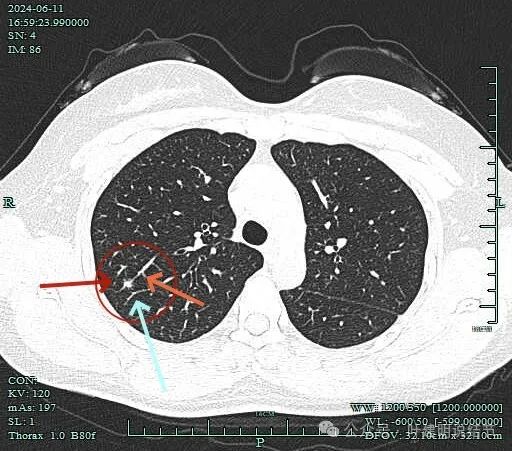

先看2024年6月的影像:

病灶虽小,但毛刺明显,而且天蓝色箭头所指的邻近血管有弯向病灶侧。